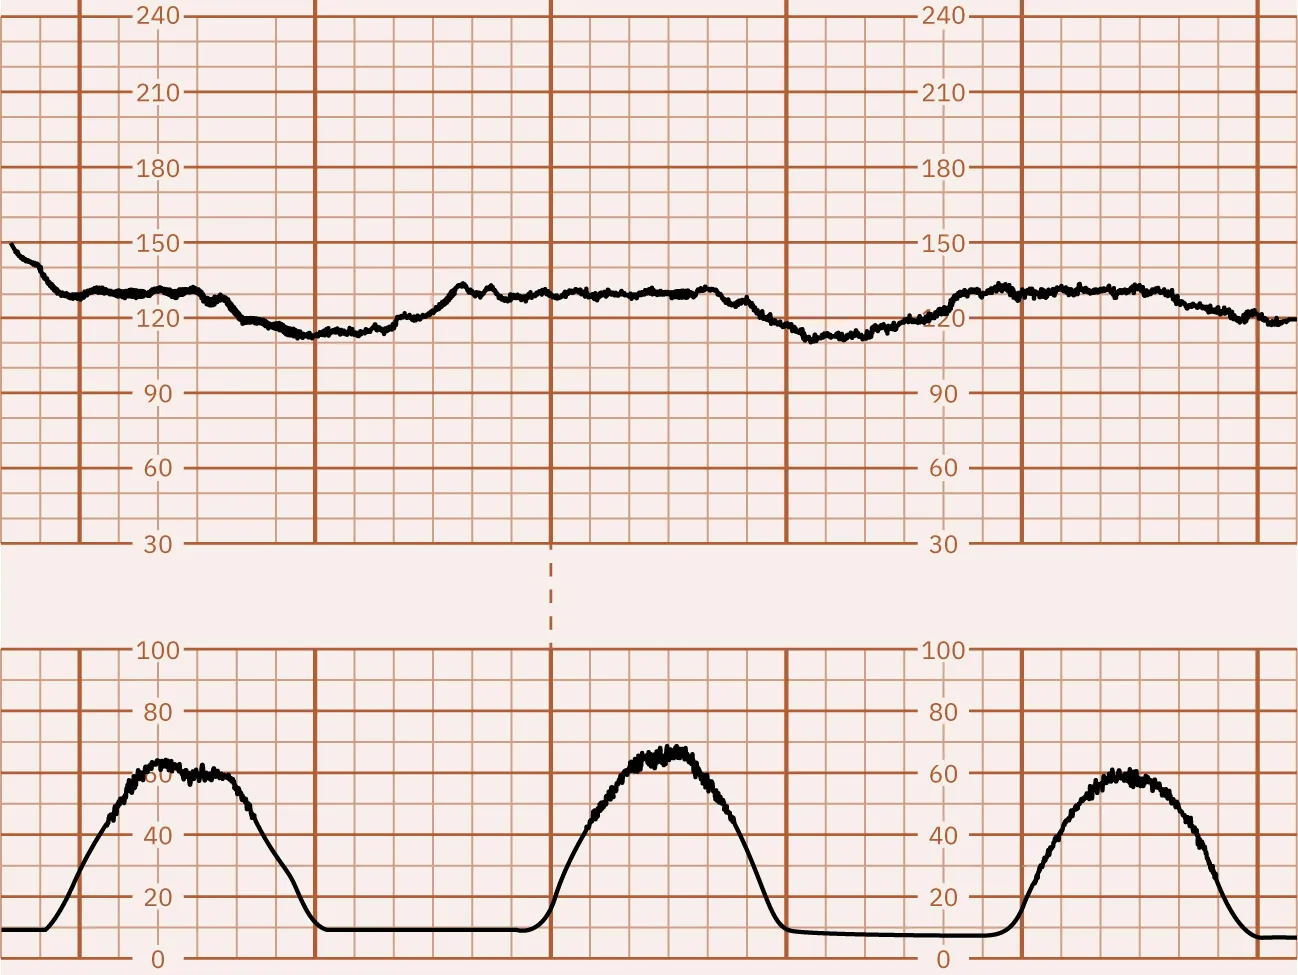

The nurse interprets the following external EFM tracing.

A tracing with the FHR in blue at the top. It ranges from 120 to 150 with occasional breaks in the line and occasional drops. The contraction tracing is at the bottom and has peaks that range from 50 to 70 from the baseline of approximately 10 and occur 2 to 3 minutes apart. FHR increases slightly at the peaks of contractions. A green line lies in the middle of the FHR and UC lines and ranges approximately from 70 to 90 with no apparent pattern.

How does the nurse document the summary of this tracing?